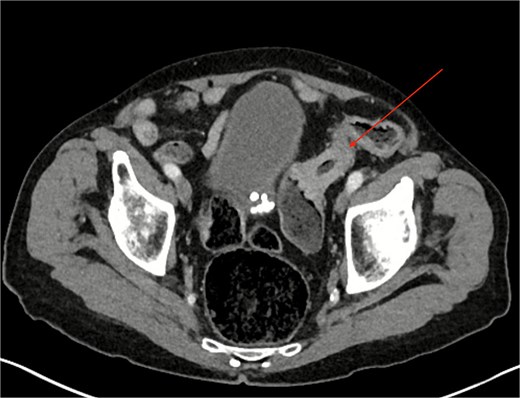

Computed tomography (CT) of the abdomen and pelvis revealed a partially obstructing apple-core lesion in the sigmoid colon suspicious for malignancy (Fig. 1). Multiple small hepatic hypodensities and a sclerotic focus in the L4 vertebra were also noted; staging CT of the chest showed no pulmonary metastases.